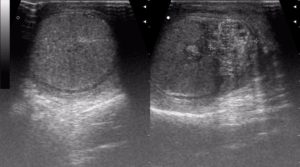

Онкологические процессы в яичке

Семинома Рак яичка встречается относительно редко, и в 95% случаев это герминогенные опухоли (в 50-60% семинома). В зависимости от гистологического типа выглядит картина: гомогенная или негомогенная структура. Патологические новообразования чаще диагностируют в правом яичке. Билатеральные опухоли (с обеих сторон) выявляются в 1-3% случаев.

Опухоль на УЗИ выглядит как образование неправильной формы, иногда состоит из нескольких новообразований, с неоднородной структурой. Размеры больного яичка больше нормы, присутствует реактивная водянка. Если есть подозрение на рак яичка, то в обязательном порядке исследуют забрюшинное пространство и регионарные лимфатические узлы для исключения или подтверждения процессов метастазирования.

Обязательно выполнение биопсии образования.